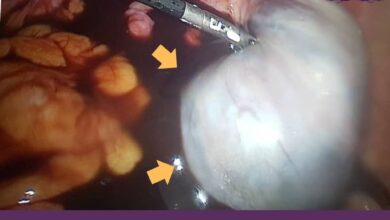

با لاپاراسکوپی به راحتی با کیست آندومتریوز خداحافظی کنید

لاپاراسکوپی آندومتریوز عمل بسیار مهمی است که برای درمان عارضه پردرد کیست آندومتریوز کاربرد ویژهای دارد. زنانی که به کیست آندومتریوز…